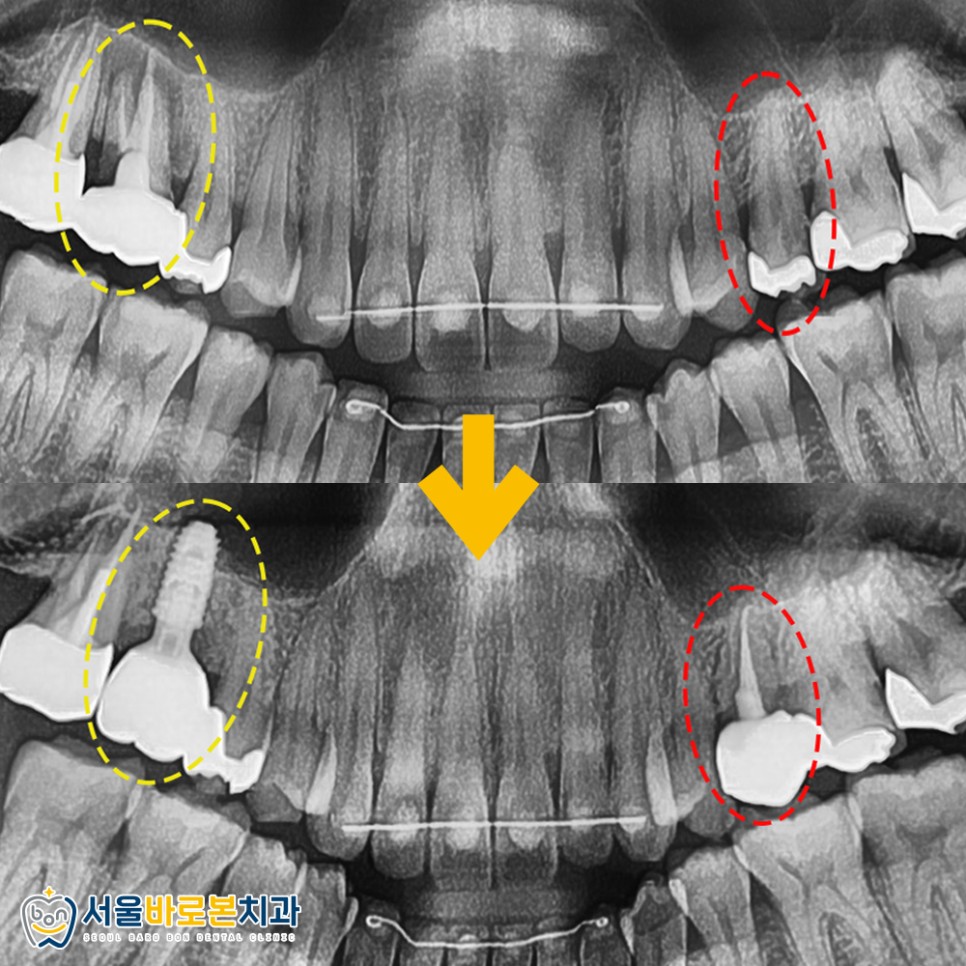

구강 내 체크를 해보니

왼쪽 치아는 과거 인레이 보철을

오른쪽 치아는 크라운 치료를

받으신 상태였는데요.

조금 더 상태를 자세하게 확인하기 위해

파노라마 방사선 사진을

촬영해 보았습니다. ^^

🔹 왼쪽 작은 어금니는 인레이 하방으로

2차 충치가 보이고,

🔹 크라운이 수복되어 있는 오른쪽 큰 어금니는

뿌리 주변으로

염증소견이 관찰되었습니다.

* X-ray 사진상으로 보이는

오른쪽이 실제로는 왼쪽이므로

참고하여 봐주시길 바랍니다.

왼쪽 작은 어금니는

신경치료 후 크라운 수복까지 완료해 드렸고

오른쪽 큰 어금니는 현재 치아 뿌리 역할을 하는

임플란트 픽스처(인공치근)만 심겨있는 모습인데요.

잇몸뼈와 픽스처가 충분히 결합되도록

기다린 후에 크라운(보철물)을 올려드리게 됩니다.